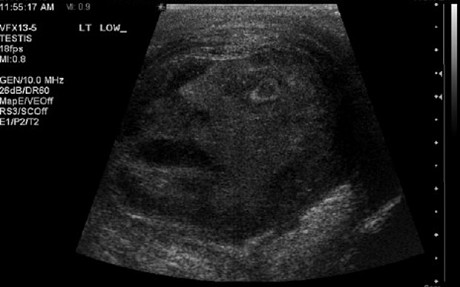

据外媒10月31日报道,加拿大安大略省的两名医生罗伯茨和托马在为一名患者做睾丸超声波检查时,成片中竟出现了一张若隐若现的“人脸”。“人脸”上有眼有鼻有嘴,正直愣愣地“盯着”两位医生。着实让医生们大吃一惊。

据悉,这名45岁的男性患者因为睾丸疼痛才来医院就医的。医生们让他去拍片以检查疼痛的成因。没想到成片竟然出现了一张“脸”,医生们在该患者的病历中描述道:“患者的成片实在令人惊讶,似乎出现了一个男子的脸。他的嘴张开着,仿佛在为看见超声波检查而惊讶,又好像是因为正在经受病症的痛苦。”

不过,医生并没有将这张意外出现的“人脸”当做神启或是神的标志。经过会诊,医生认为该患者得了比较严重的附睾睾丸炎。